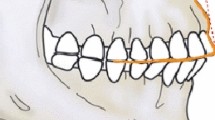

Virtual simulation was applied to visualize the distribution and direction of the debridement routes (Figs. 2C, D, and 4E; Fig. S3). The fundamental principle of debridement route design for CDI is to achieve maximal effectiveness with minimal tissue damage. This principle could be illuminated as the MICRO principle, which comprises the following key aspects: 1) Maximum mechanical (M) debridement. 2) Maximum chemical irrigation (I). 3) Optimal and accurate access cavity (C). 4) The most convenient rectilinear (R) route. 5) Minimal obstruction (O). In alignment with these aspects, the number of opening access cavities should be appropriate, the location should be accurate, and the interval should be reasonable. Well-designed debridement routes allow the instruments to enter rectilinearly, avoid obstruction, and maximize contact between the instruments and infected pulp tissue for efficient mechanical debridement and chemical irrigation.

Inspired by the 3-Determination principle, which involves determining the location, depth, and instrumentation angle in the management of calcified root canals [26], a personalized improvement was made to the templates compared to several CDI cases using the GE technique (Table 1). Besides verifying valid access location and direction, the ideal operating depth was also achieved by adjusting the height of the resin sleeve in the templates (Fig. 2K). When the bur was fully inserted into the cylinder, it reached the pulp cavity. This enhancement is advantageous, particularly for less experienced endodontists, as it reduces hesitation during the operation and allows for maximum dental structure preservation.